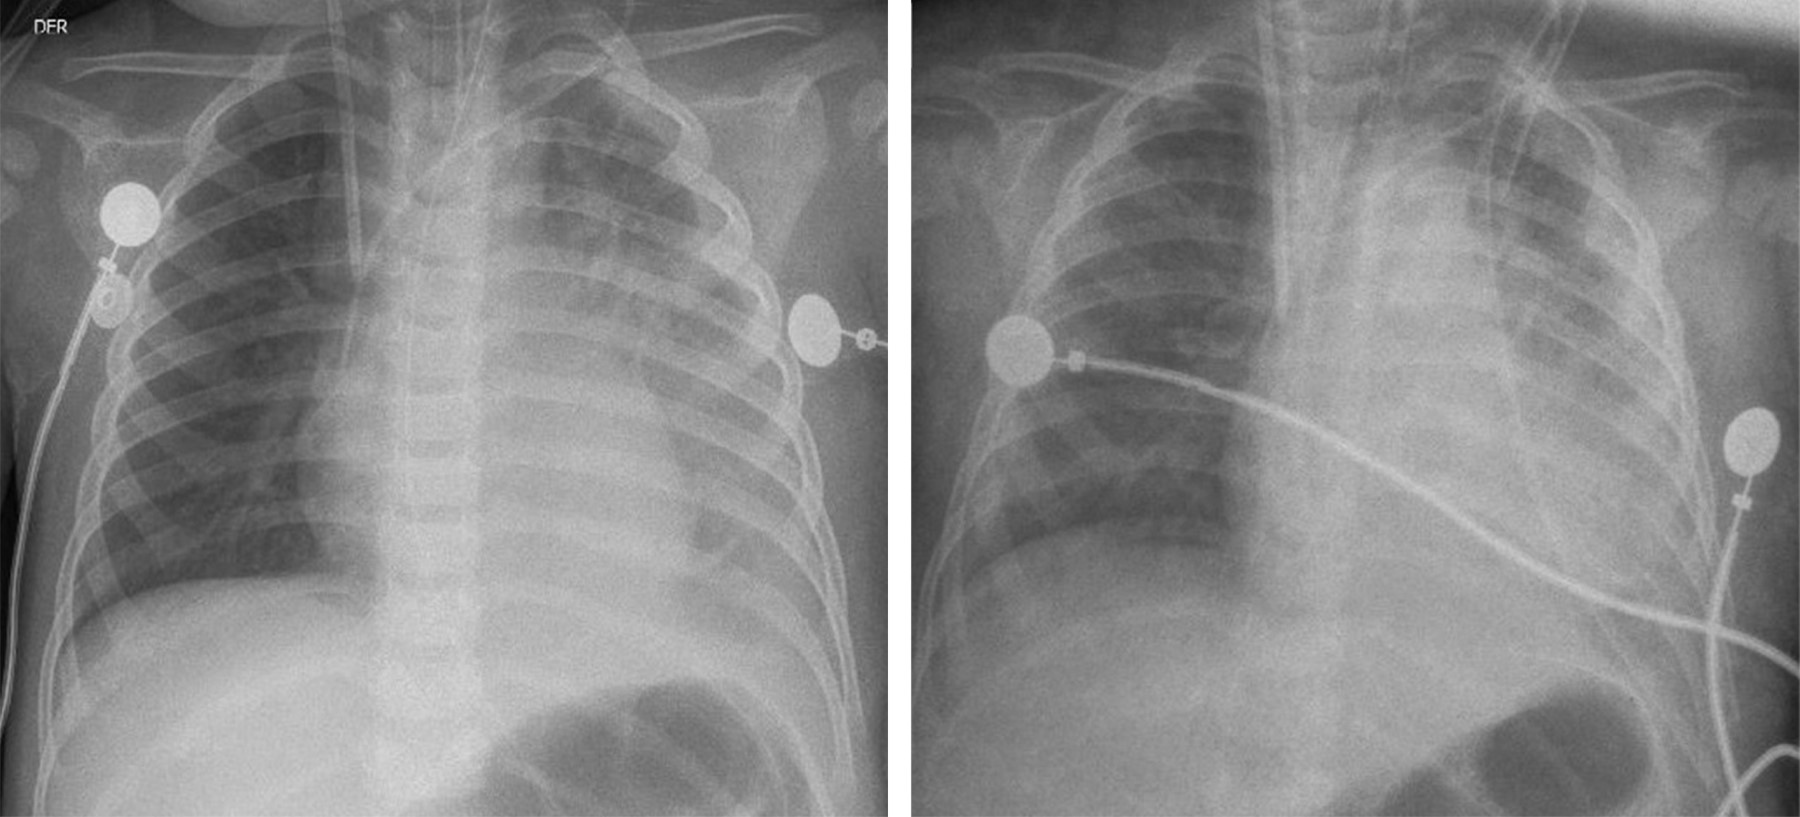

Los estudios serológicos para hepatitis A, B, C, citomegalovirus, virus de Epstein-Barr y virus del herpes simple fueron negativos. La radiografía de tórax mostró neumonía en base pulmonar izquierda y derrame pleural (Figura 1), por lo que se inicia manejo antibiótico con ceftriaxona y clindamicina.

Figura 1